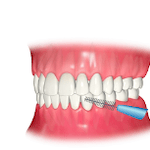

・歯磨き、フロス、歯間ブラシ

歯周病(歯槽膿漏)治療の基本は歯磨きによる歯周病菌の除去です。歯磨きやフロスでお口の中の汚れの約8割が取り除けます。

残りの汚れは日頃の磨き残しや歯周ポケットの内側に溜まってこびりつき硬くなってしまうので、歯科医院に来ていただいた時にお取りしていきます。

お家で8割、歯科医院で2割、合わせて10割取っていくことで歯周病を予防しましょう。

ホームケアとはお家で行う普段の歯磨きのことです。虫歯や歯周病を予防するための食習慣もホームケアの一環です。このホームケアが上手くいっていないと治療の効果が出にくかったり、歯周病が再発する可能性が高くなります。

◉ 歯磨き、フロス、歯間ブラシなど